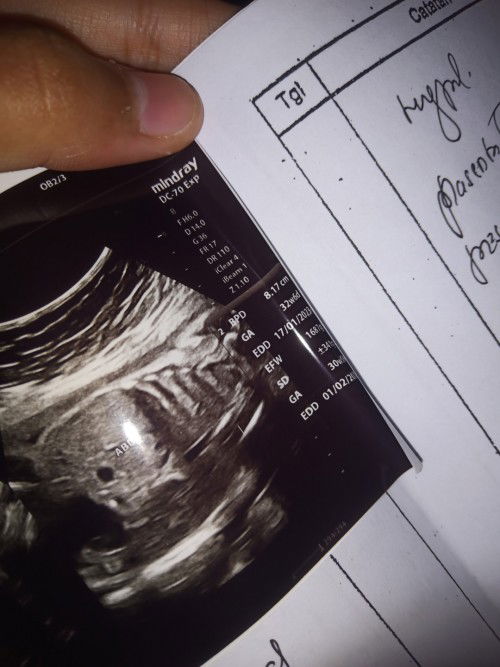

Mau tanya nih kak soal usia kehamilan

Kemarinkan saya habis usg ya kak, kata dokter semuanya normal allhamdulillah, yg jadi pertanyaannya usia kandungan saya ternyata suda 32 minggu lebih, tapi tercantum di apk ini 29 jadi saya was was pantesan perut sering mules2, saya jadi bingung, bingung mana yg bener huhu. Kalo ada yang sama gimana ya kak share